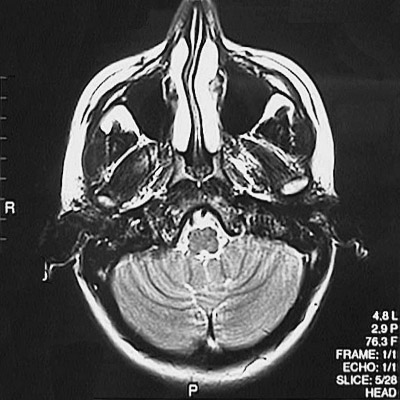

This is a normal axial T2 weighted MRI scan demonstrating the nasal septum and concha and maxillary sinus and medulla and fourth ventricle and cerebellar hemisphere and external auditory canal.